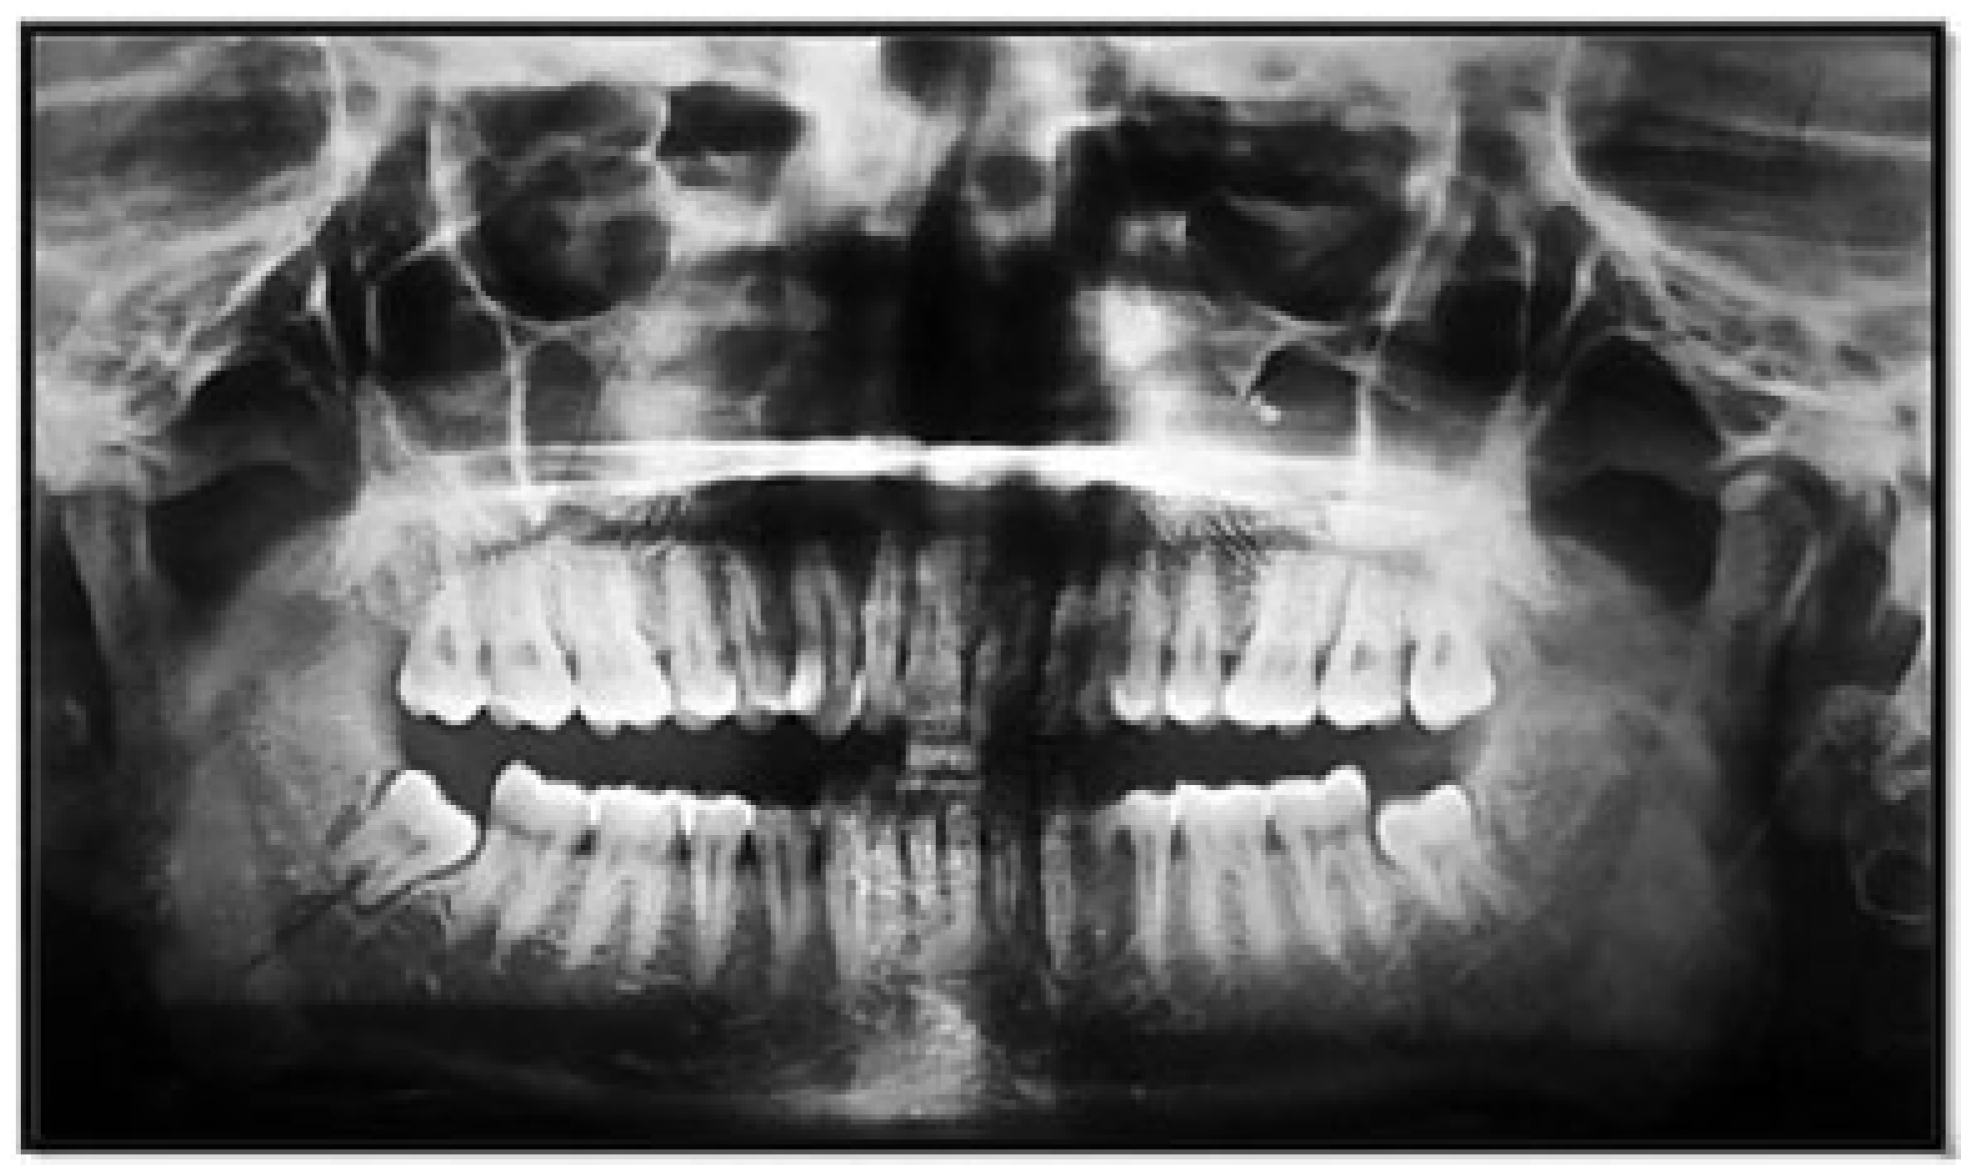

Figure 9. Angle fracture with mesioangular class II position B impaction.

Of the 146 mandibular angle fracture patients who had a lower third molar, the highest incidence was seen in mesioangular angulation (105 patients; 71.92%) followed by horizontal angulation (29 patients; 19.86%), vertical angulation (10 patients; 6.85%), and distoangular angulation (2 patients; 1.37%), respectively.

Of the 54 mandibular condyle fracture patients, who had a lower third molar, the highest incidence was seen in vertical angulation (34 patients; 62.96%) followed by mesioangular angulation (13 patients; 24.07%), distoangular angulation (5 patients; 9.26%), and horizontal angulation (2 patients; 3.70% [Figure 9, Figure 10 and Figure 11; Table 5]), respectively.